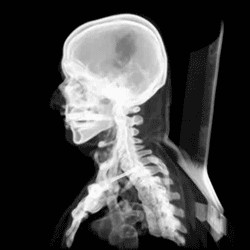

At birth, the human skull is made up of 44 separate bony elements. During development, many of these bony elements gradually fuse together into solid bone (for example, the frontal bone). The bones of the roof of the skull are initially separated by regions of dense connective tissue called fontanelles. There are six fontanelles: one anterior (or frontal), one posterior (or occipital), two sphenoid (or anterolateral), and two mastoid (or posterolateral). At birth, these regions are fibrous and moveable, necessary for birth and later growth. This growth can put a large amount of tension on the "obstetrical hinge", which is where the squamous and lateral parts of the occipital bone meet. A possible complication of this tension is rupture of the great cerebral vein. As growth and ossification progress, the connective tissue of the fontanelles is invaded and replaced by bone creating sutures. The five sutures are the two squamous sutures, one coronal, one lambdoid, and one sagittal suture. The posterior fontanelle usually closes by eight weeks, but the anterior fontanel can remain open up to eighteen months. The anterior fontanelle is located at the junction of the frontal and parietal bones; it is a "soft spot" on a baby's forehead. Careful observation will show that you can count a baby's heart rate by observing the pulse pulsing softly through the anterior fontanelle.

The skull in the neonate is large in proportion to other parts of the body. The facial skeleton is one seventh of the size of the calvaria. (In the adult it is half the size). The base of the skull is short and narrow, though the inner ear is almost adult size.[15]